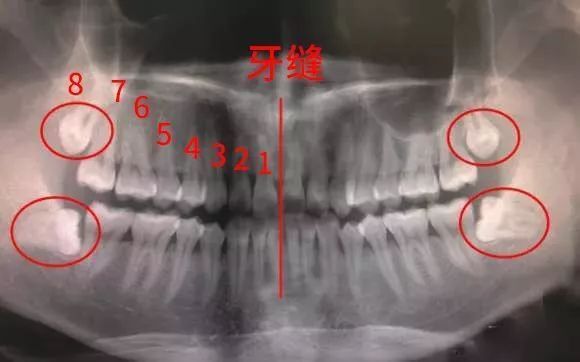

一般最多可长4颗,分别在上下两排牙齿的左右最里面那一颗。具体发育几颗因人而异,有些人4颗都长齐了。